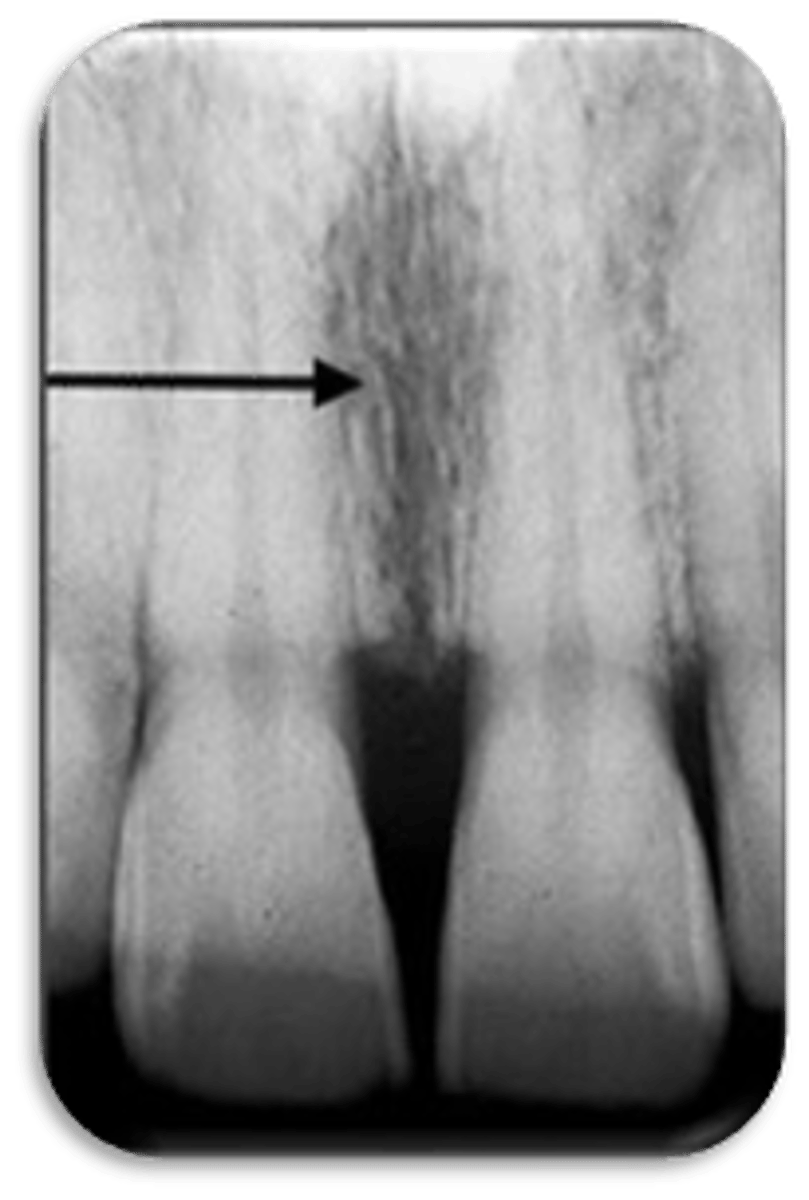

intermaxillary suture

ID the structure:

nasopalatine foramen